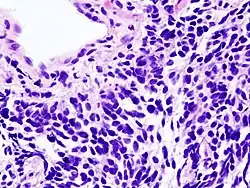

Micrograph of a small-cell carcinoma of the lung showing cells with nuclear moulding, minimal amount of cytoplasm and stippled chromatin. FNA specimen. Field stain.

Histopathology of small-cell carcinoma, with typical findings.[31]

Histopathologic image of small-cell carcinoma of the lung. CT-guided core needle biopsy. H&E stain.

Small-cell carcinoma is an undifferentiated neoplasm composed of primitive-appearing cells. As the name implies, the cells in small-cell carcinomas are smaller than normal cells and barely have room for any cytoplasm. Some researchers identify this as a failure in the mechanism that controls the size of the cells.[32]